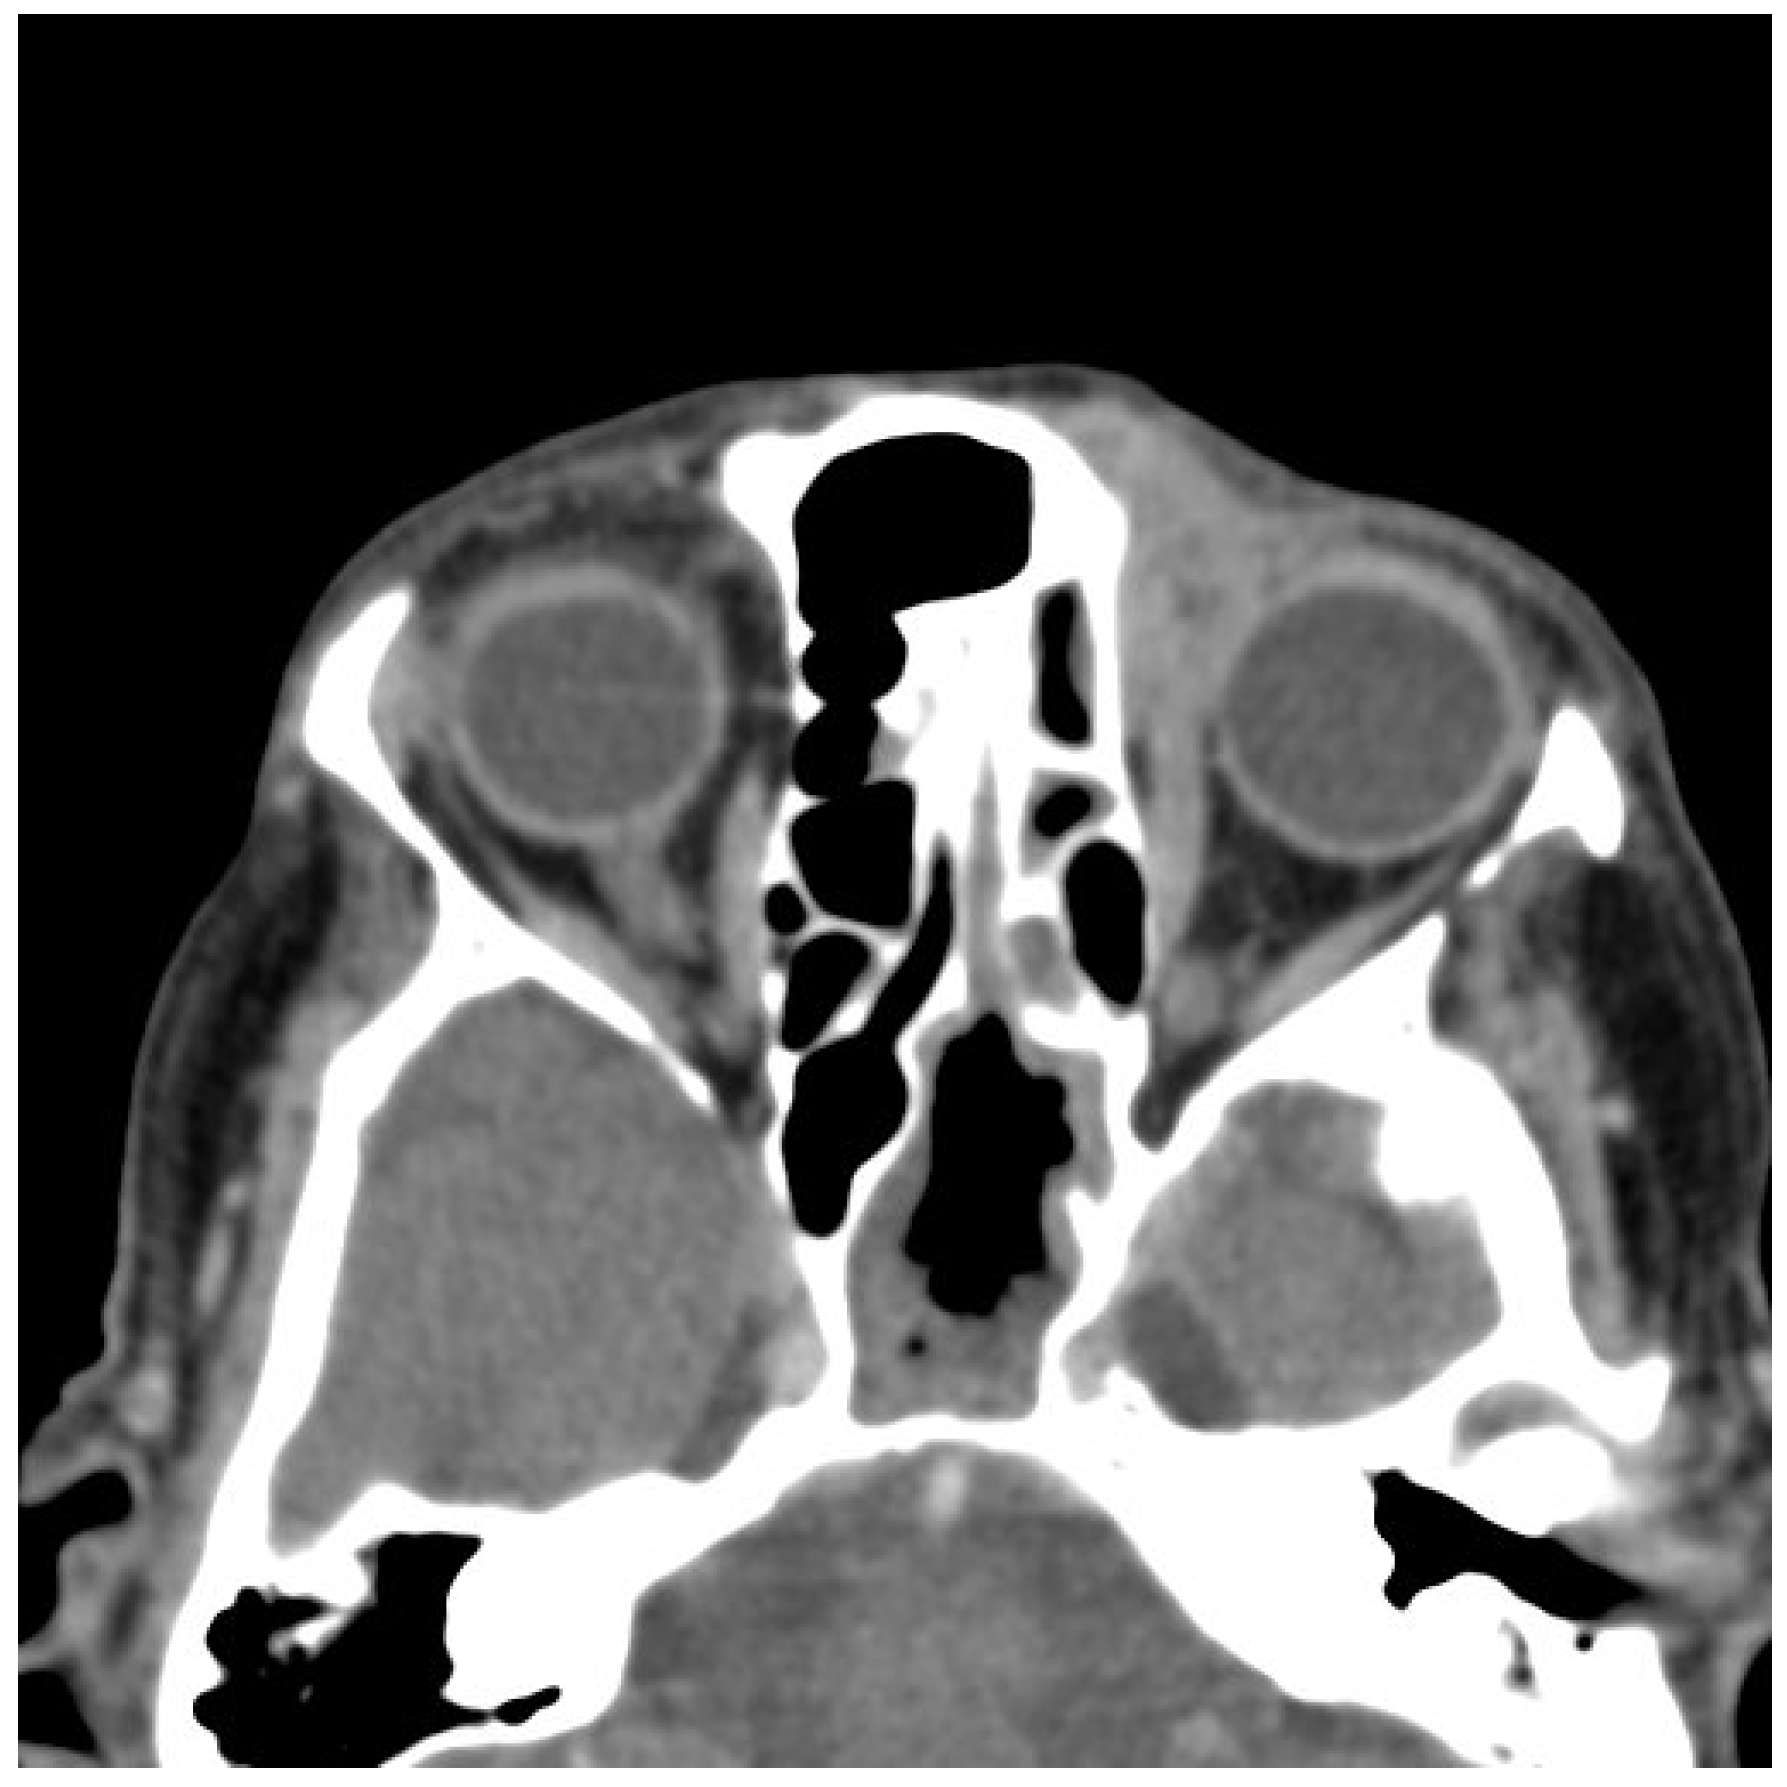

2.2. Imaging and Preoperative Diagnostics